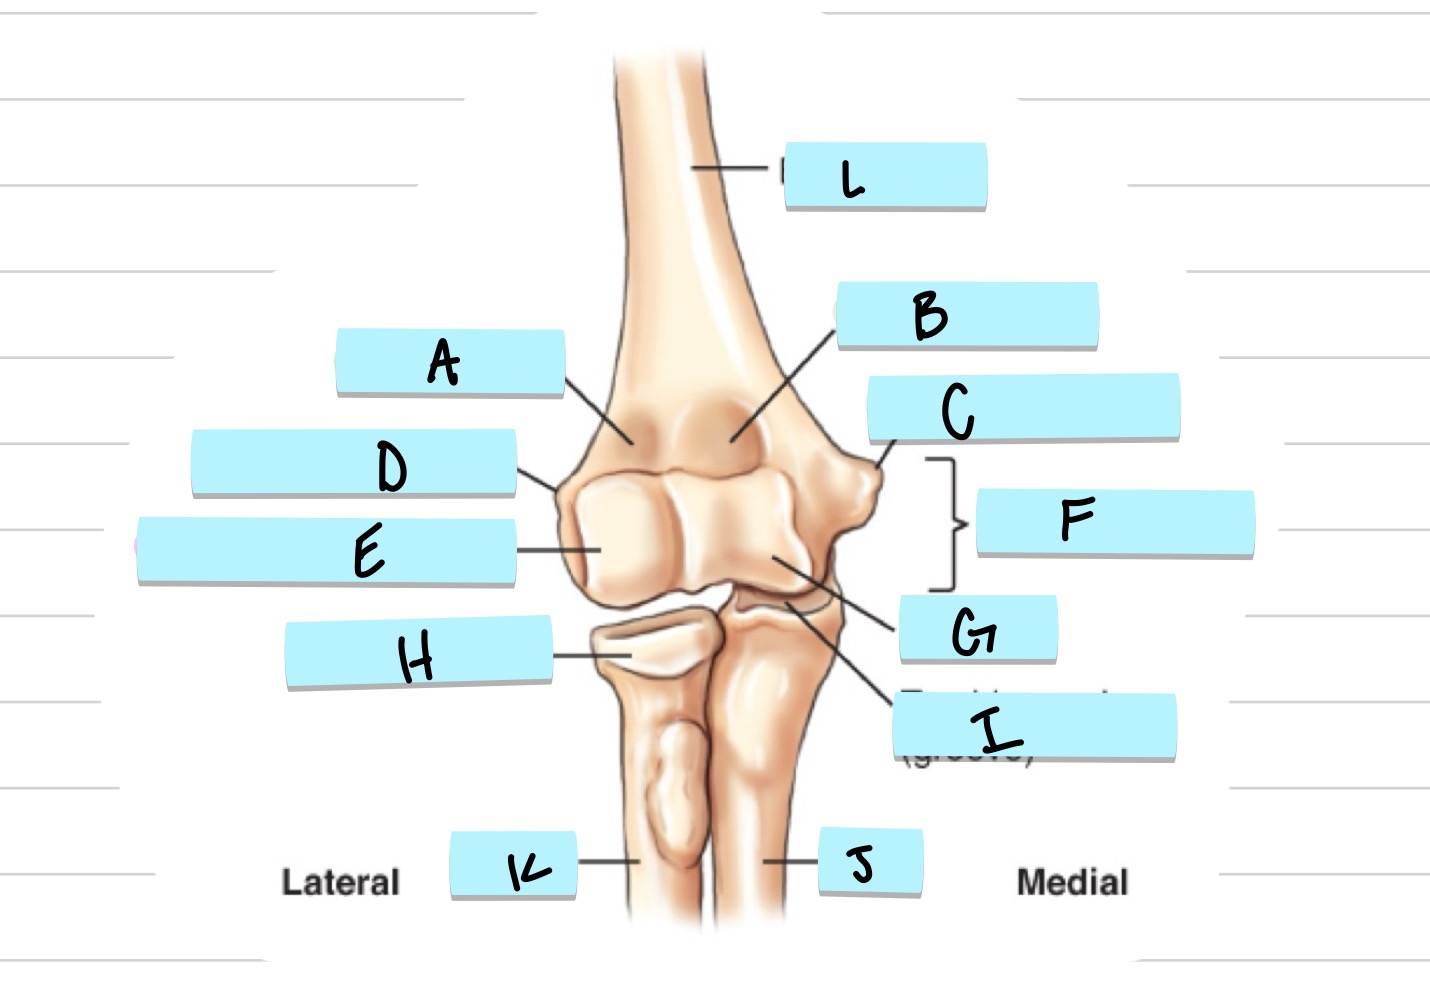

<p>What is A?</p>

What is A?

olecranon process

New cards

<p>what is B?</p>

what is B?

trochlear notch

37

<p>what is C?</p>

what is C?

coronoid process

38

<p>what is D?</p>

what is D?

radial notch

radial fossa

83

coronoid fossa